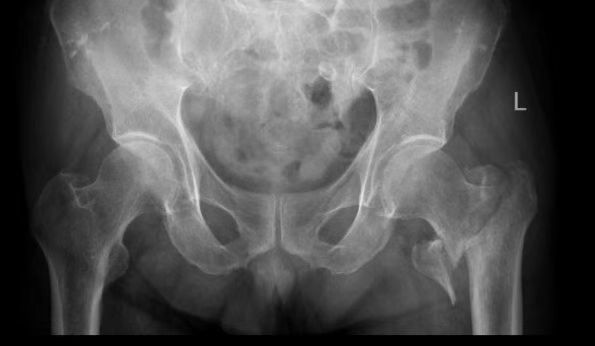

患者张爷爷已逾九旬,基础疾病错综复杂:前列腺癌病史3年、高血压20年、糖尿病30年,10天前因脑梗死导致左侧肢体活动不便。然而近日,厄运再次降临,他在家如厕时不慎跌倒,造成“左侧股骨转子间粉碎型骨折”,被紧急送至该院。

入院时,老人情况十分危急:除骨折外,还存在Ⅰ型呼吸衰竭、慢性支气管炎急性加重、低钠血症及贫血等疾病。入院后其呼吸功能进一步恶化,随即被转入ICU,进行气管插管、呼吸机辅助呼吸。经过ICU团队5天昼夜不停的全力救治,张爷爷的呼吸功能终于显著改善,成功拔管,脱离了生命危险。

ICU与呼吸内科团队确保患者拔管后呼吸功能稳定;心血管内科、内分泌科精准调控血压、血糖至精准范围;神经内科评估患者脑梗后状态。手术麻醉科量身定制创伤最小、最稳定的个性化麻醉与监测方案,严阵以待可能出现的循环和呼吸波动。在此基础上,骨科团队最终决定采用微创的“闭合复位髓内钉内固定术”,力求以最短时间、最小创伤完成固定。

在万全准备下,手术如期展开。术中,多学科团队配合默契,操作精准流畅。仅用时40分钟便成功完成骨折复位与固定,术中出血极少,患者生命体征平稳。这场高风险手术取得了关键性胜利。